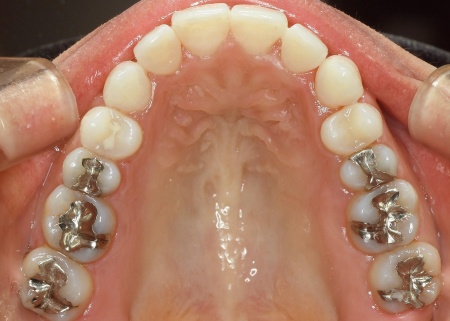

「奥歯で噛むと上下前歯が触れ合わないので、噛み合わせを治したい。また、歯並びがデコボコしているのも気になる」とご相談いただきました。

拝見したところ、奥歯で噛んだ際に上下の前歯が触れ合わず、隙間ができている状態でした。

これは開咬(かいこう)と呼ばれ、前歯で食べ物を噛み切るのが難しい噛み合わせです。

加えて全体的に歯が重なり合ってデコボコに生えており、歯磨きがしにくく、審美性にも悪影響がでています。

さらに舌で前歯を押す癖もあり、これは開咬の原因だけでなく、矯正治療後に歯並びが戻る原因にもなります。